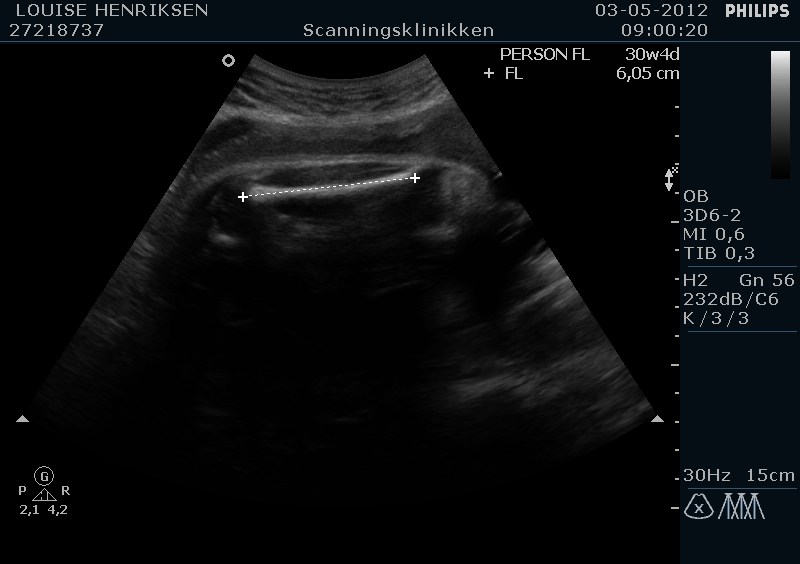

I dag skulle manden overraskes med en 4 d scanning.... og hans far var også med det var også en overraskelse, samt den lille prins....han fik bind for øjene og vi kørte mod scanning klinikken.... vi fik nogle gode sekvenser af bettemanden.. men han fylder en del derinde nu, så billederne blev ikke voldsomt gode.. men nogle fik vi dag...jeg skulle i morgen være 32 fulde uger.. mne scanningen i dag vidste34+4 dage yiarks.... jeg skal til at være færdig med den bachelor..... han vejede efter målene 1871 gram.....

Men det er da en lille vægt hvis du sku være så langt? Min lillefis blev skønnet til 2300 g da jeg var 34+0, og det sagde jm var lige på gennemsnittet.. Mon ikke der kan være sket en tastefejl hos scanningen?